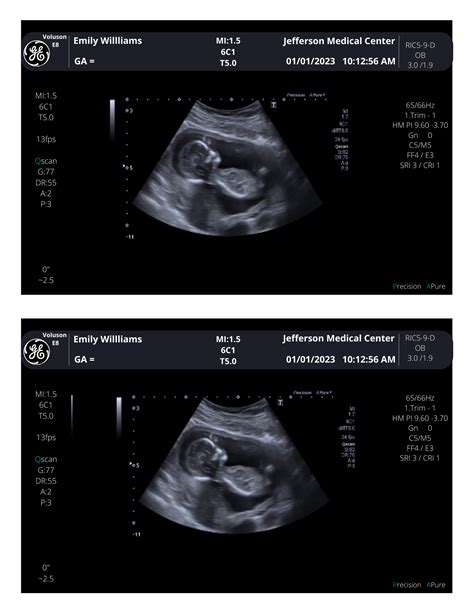

Ultrasound scan of a fetus

The 11 week ultrasound is typically performed either abdominally or transvaginally, depending on factors such as your body type and the position of the uterus. For most women at 11 weeks, an abdominal ultrasound is sufficient, where a transducer is moved over the belly with gel. However, if a clearer image is needed, a transvaginal approach may be used. The entire process is generally painless, though it can feel a bit cold due to the conductive gel.

During the appointment, the sonographer or doctor will focus on several key aspects to ensure the pregnancy is progressing as expected. They are not just looking for a heartbeat; they are assessing anatomical development and ensuring the pregnancy is located safely within the uterus. It is a moment of wonder for many, as you can often see the baby moving, though you may not feel those movements yet.

By the 11th week, your baby is roughly the size of a lime or a Brussels sprout, measuring about 1.5 to 2 inches long. Despite their small size, they are incredibly active. During the 11 week ultrasound, you might be surprised to see your baby performing various movements, such as curling their toes, stretching, or even hiccuping.

• Movement: You will likely see the baby wriggling and stretching, which is a sign of healthy neuromuscular development.